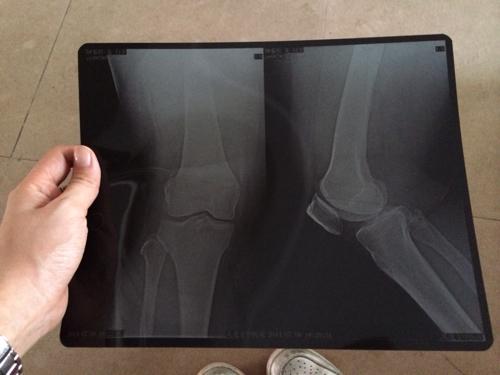

妈妈膝盖一直吵着说痛,今天去照x光,医生说是骨质增生,想问问各位专家

膝关节骨质增生图片

骨质增生膝盖